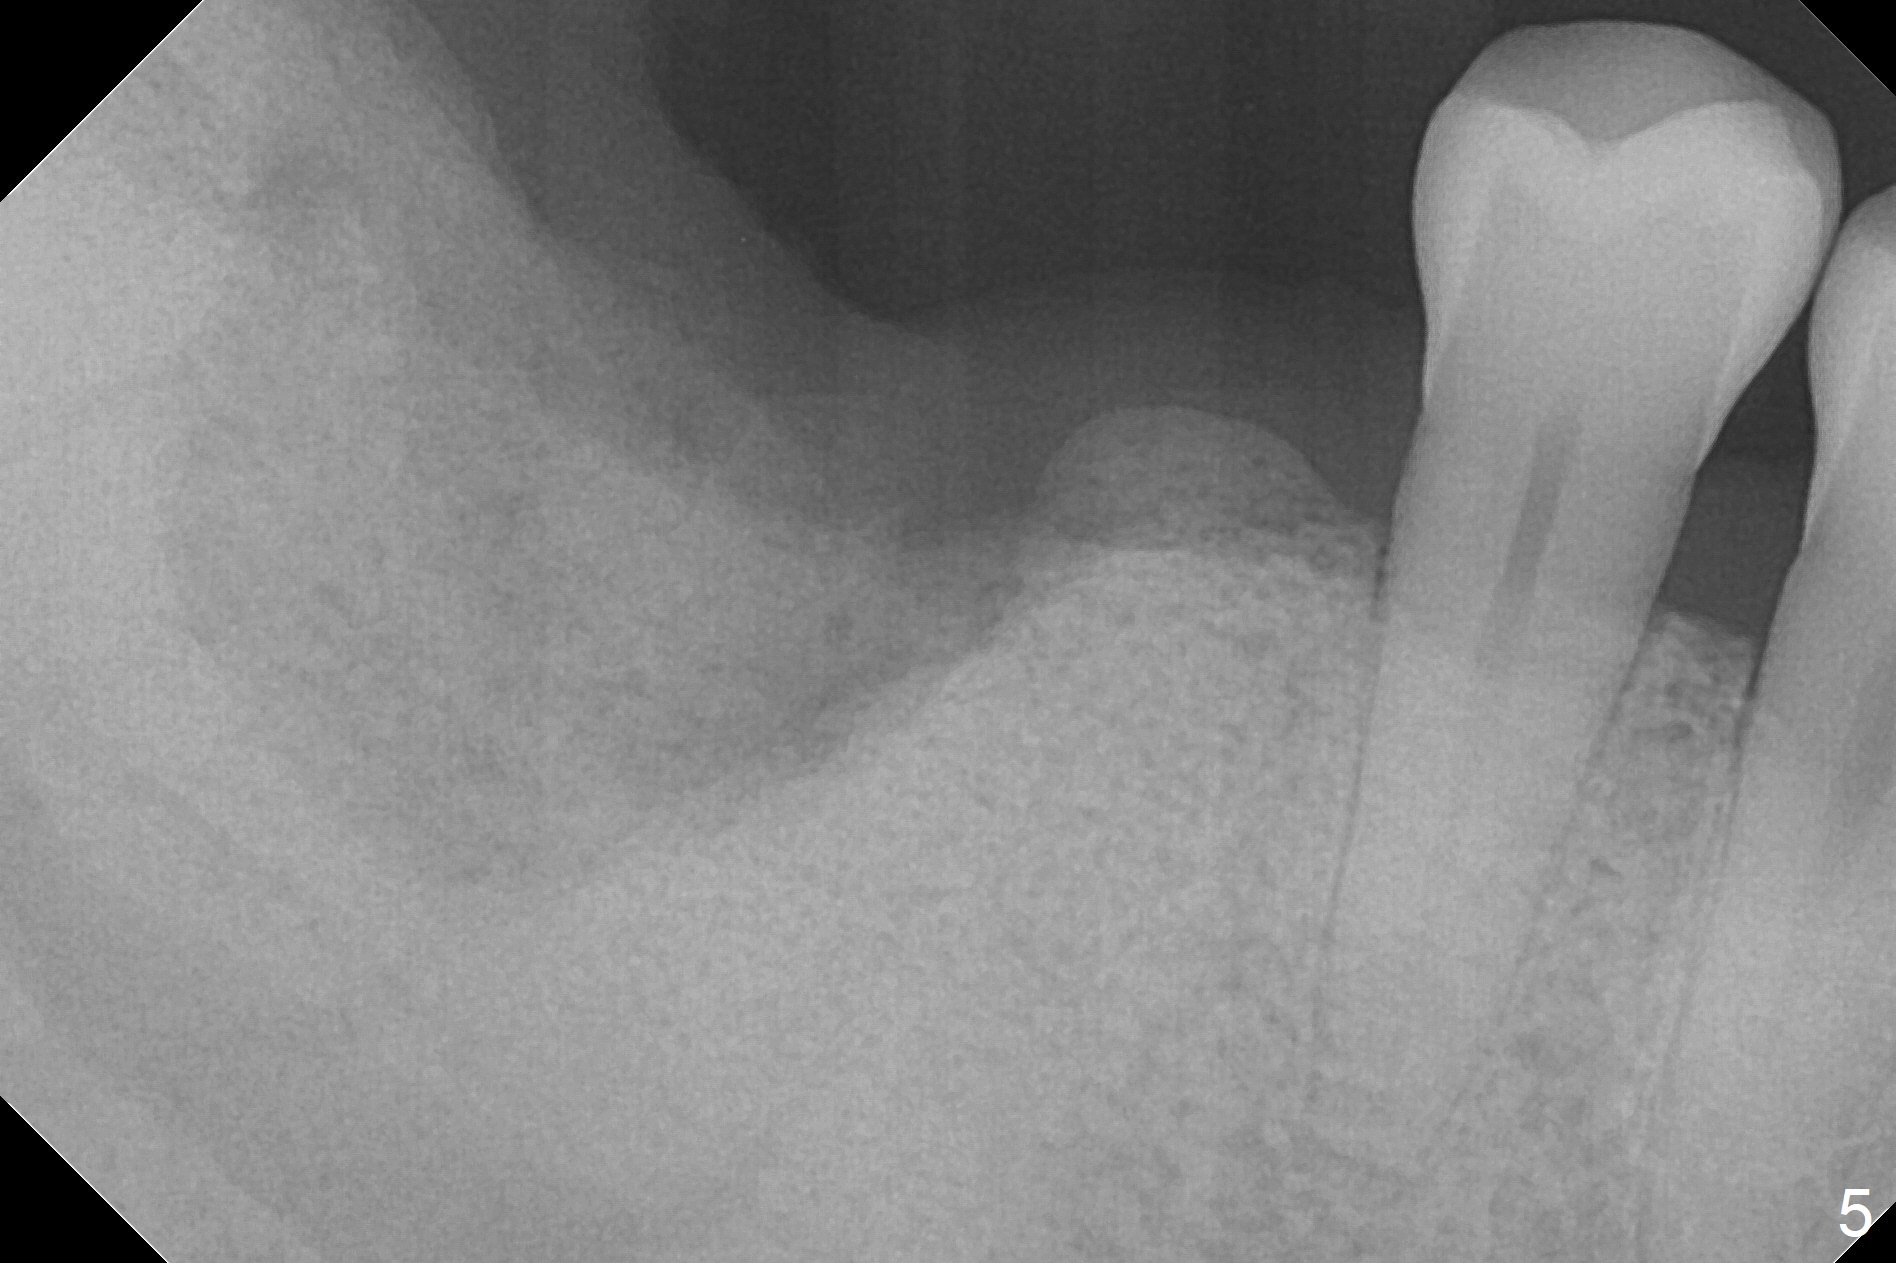

Extraction of the mobile tooth #31 (Fig.1) and debridement of the large socket are not difficult. But making osteotomy buccally does not seem to be easy. It will be difficult to restore. Instead, socket preservation is accomplished by filling the socket with approximately 1.5 cc of Mineralized Cortical/Cancellous allograft until the crest (Fig.2,5). The socket opening is closed by insertion of 4 pieces of PRF membranes (Fig.3) and 4-0 Chromic gut sutures (Fig.4). In the end of surgery, it appears that osteotomy in the center of the socket could be a better approach. Postop re-analysis of CT (Fig.6) and PA (Fig.7) shows that there is 3.9 mm of the native bone to support a 5.5x10 mm implant. Sinus Lift Master Kit should be used with 2 mm initial drill and 2.8 and 3.6 mm round drills with 4 mm stopper.

The socket heals 3 months postop (Fig.8,11). There is vertical loss of the ridge at #31 (Fig.9,10). The implant placed at #31 will be shorter than that at #30 (Fig.12). The patient will return for implant placement 4 months postop.